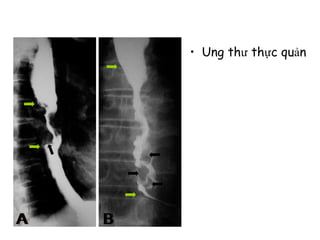

• Ung thư thực quản

• Ung thưthực quản